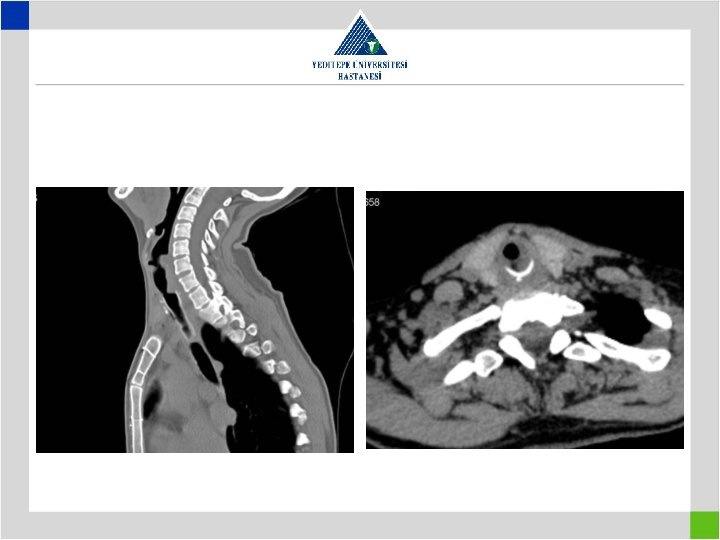

Iatrogenic Factors • Metal stents in bening tracheal conditions cause elongation of pathologic segment and cause the patient to loose the previously present chance of surgical cure